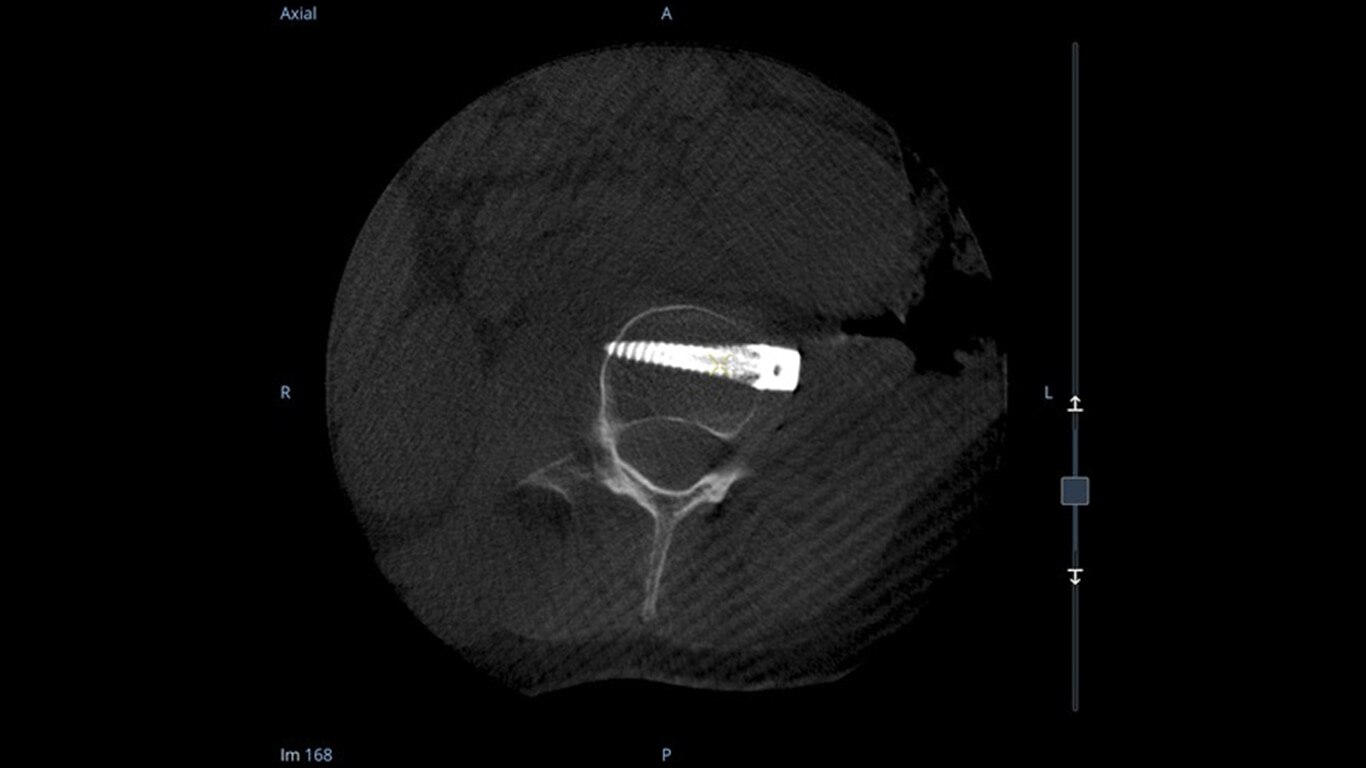

Enhance intraoperative decision-making with visualization capabilities of Augmented Fluoroscopy in the OEC 3D Volume Viewer. Analyze five perspectives with 3D imaging tools including Multi-Oblique Mode, scrolling 512 slices, zoom, and more.

See more levels during a spinal fusion, or more of the pelvis or femur during an orthopedic procedure. With a 19 cm x 19 cm x 19 cm volume, OEC 3D captures a 67% greater volume than other 3D C-arms*.